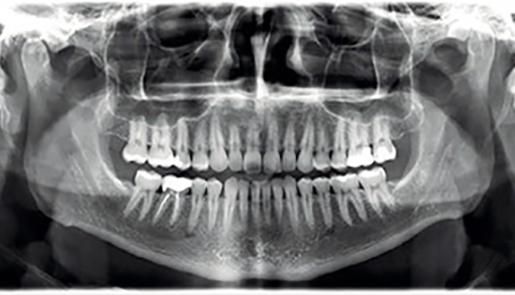

Panoramaröntgen und DVT

strahlenreduziertes 3D Zahnröntgen am Zahnambulatorium Wienerberg City in Wien

Mit unseren hauseigenen digitalen Volumentomographen werden Panoramaröntgen, 3D-(DVT)-Bilder und Kleinbilder bei niedriger Strahlenbelastung in höchster Auflösung und Qualität dargestellt.